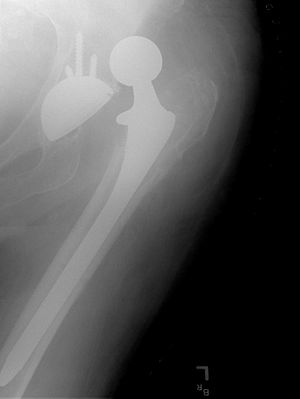

صورة بأشعة إكس، مفصل المريض (يسار الصورة) تم استبداله، with the ball of this ball-and-socket joint replaced by a metal head that is set in the thighbone or femur and the socket replaced by a white plastic cup (clear in this X-ray). Pelvic anatomy consistent with that of a female (large infrapubic angle, large pelvic opening).